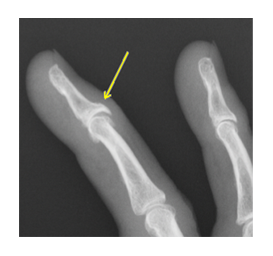

ヘバーデン結節とブシャール結節は、どちらも指の関節に起こる変形性関節症で、ヘバーデン結節は指の第一関節(DIP関節)、ブシャール結節は第二関節(PIP関節)に痛み、腫れ、変形が生じる病気です。